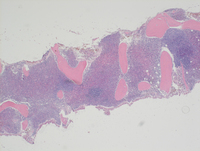

Bone core biopsy findings

Bone core biopsy shows hypercellular marrow with estimated cellularity of 90% which on higher power is notable for patchy discrete clusters of large mononuclear cells seen throughout the bone core biopsy.